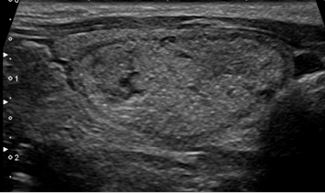

Lisa/Regular:

Borda curvilínea ininterrupta, bem definida, tipicamente de formato esférico ou elíptico.